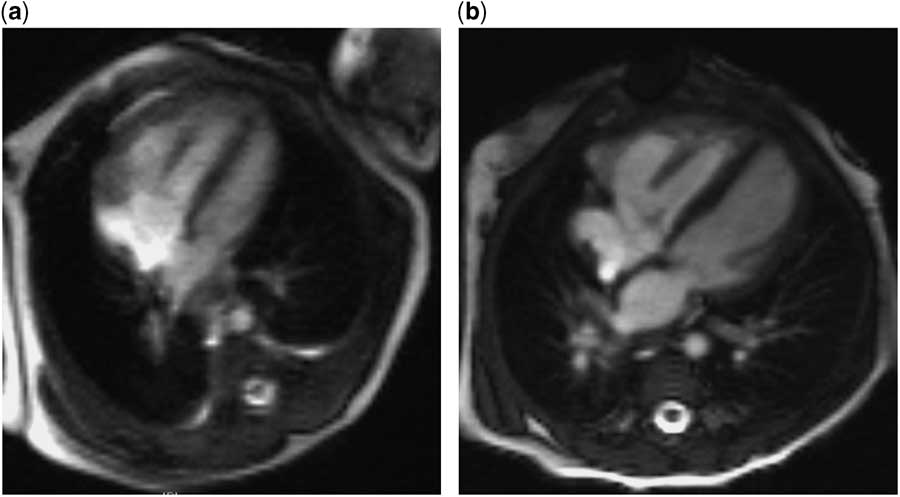

The child was born at term, with birthweight 2.89 kg, oxygen saturations 98–100% preductally and 78–84% postductally. Echocardiography demonstrated a nearly apex-forming left ventricle and small mitral (annulus 7.0 mm, z score −4.3) and aortic (annulus 4.8 mm, z score −4.6) valves. Prostaglandin E1 treatment was started to ensure systemic perfusion. Postnatal MRIs (Fig 2) showed an indexed left ventricular end-diastolic volume of 27 ml/m2 on the 1st day of life and 35 ml/m2 at 1 week, a gradual increase in pulmonary blood flow, yet no associated increase in left ventricular output. Notwithstanding, prostaglandin treatment was discontinued to assess whether a biventricular circulation was feasible following closure of the arterial duct, although this resulted in poor systemic perfusion with metabolic deterioration. At 9 days of life, the child underwent a hybrid procedure, consisting of bilateral pulmonary artery banding and ductal stenting.

Figure 2 Postnatal cardiac MRI images of the four-chamber view. ( a ) At day 1 of life, the left ventricle appears small and has an indexed left ventricular end-diastolic volume (LVEDVi) of 27 ml/m2, and measured ascending aortic flow is 1.57 L/minute/m2. ( b ) At 4.5 months of life, subsequent to a neonatal hybrid procedure of bilateral pulmonary artery banding and arterial ductal stenting, the left ventricular size appears normal, with an LVEDVi of 62 ml/m2, and ascending aortic flow is 3.14 L/minute/m2.

Cardiac MRI at 4 months of age demonstrated further growth of the left ventricle, with a left ventricular end-diastolic volume index of 62 ml/m2, and ascending aortic flow in excess of 3 L/minute/m2. Echocardiography showed no inflow or outflow obstruction and mitral valve diameter 2.8 SDs below the mean. In view of the encouraging investigations, the child underwent elective biventricular repair at 5 months of age, including arch reconstruction, duct ligation, and atrial septal defect creation. She made an uneventful recovery and is clinically well, gaining weight appropriately, on no cardiac medications 18 months later. She has mild residual mitral and aortic valvar stenosis, but there is no evidence of pulmonary hypertension.